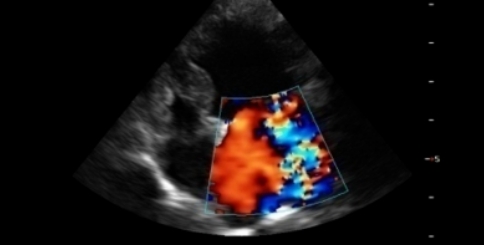

초음파 검사

복부/심장 초음파 검사는 복강 내에 존재하는

장기들은 물론 혈관과 같은 작은 구조물,

심장의 움직임 및 구조까지 실시간으로

평가할 수 있는 비침습적인 검사입니다.

심장 초음파

이럴 때 필요해요.

호흡곤란, 운동 불내성, 기절과 같은 임상증상을

보이는 경우

심장초음파 검사가 필요 할 수 있습니다.

동맥관개존증

이첨판폐쇄부전

심장사상충증